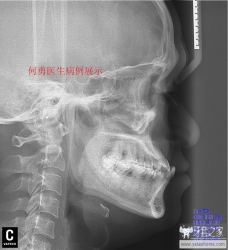

直面型

我们正畸医生追求的理想面型。建议牙套们将Gonzales-Ulloa零子午线和Ricketts审美平面区结合起来判断你是否是直面型。下面用病例展示的方式告诉牙套如何才是直面型。

突面型,

有两种,一种是骨性的,整个上颌骨向前突出

或者下颌骨发育不足,此病例为患儿有严重的咬下唇习惯导致牙性前突,骨性下颌骨发育不良(此患者人在甘肃,关于治疗效果有后续报道)

另一种是牙性的,也就是我们常说的龅牙。